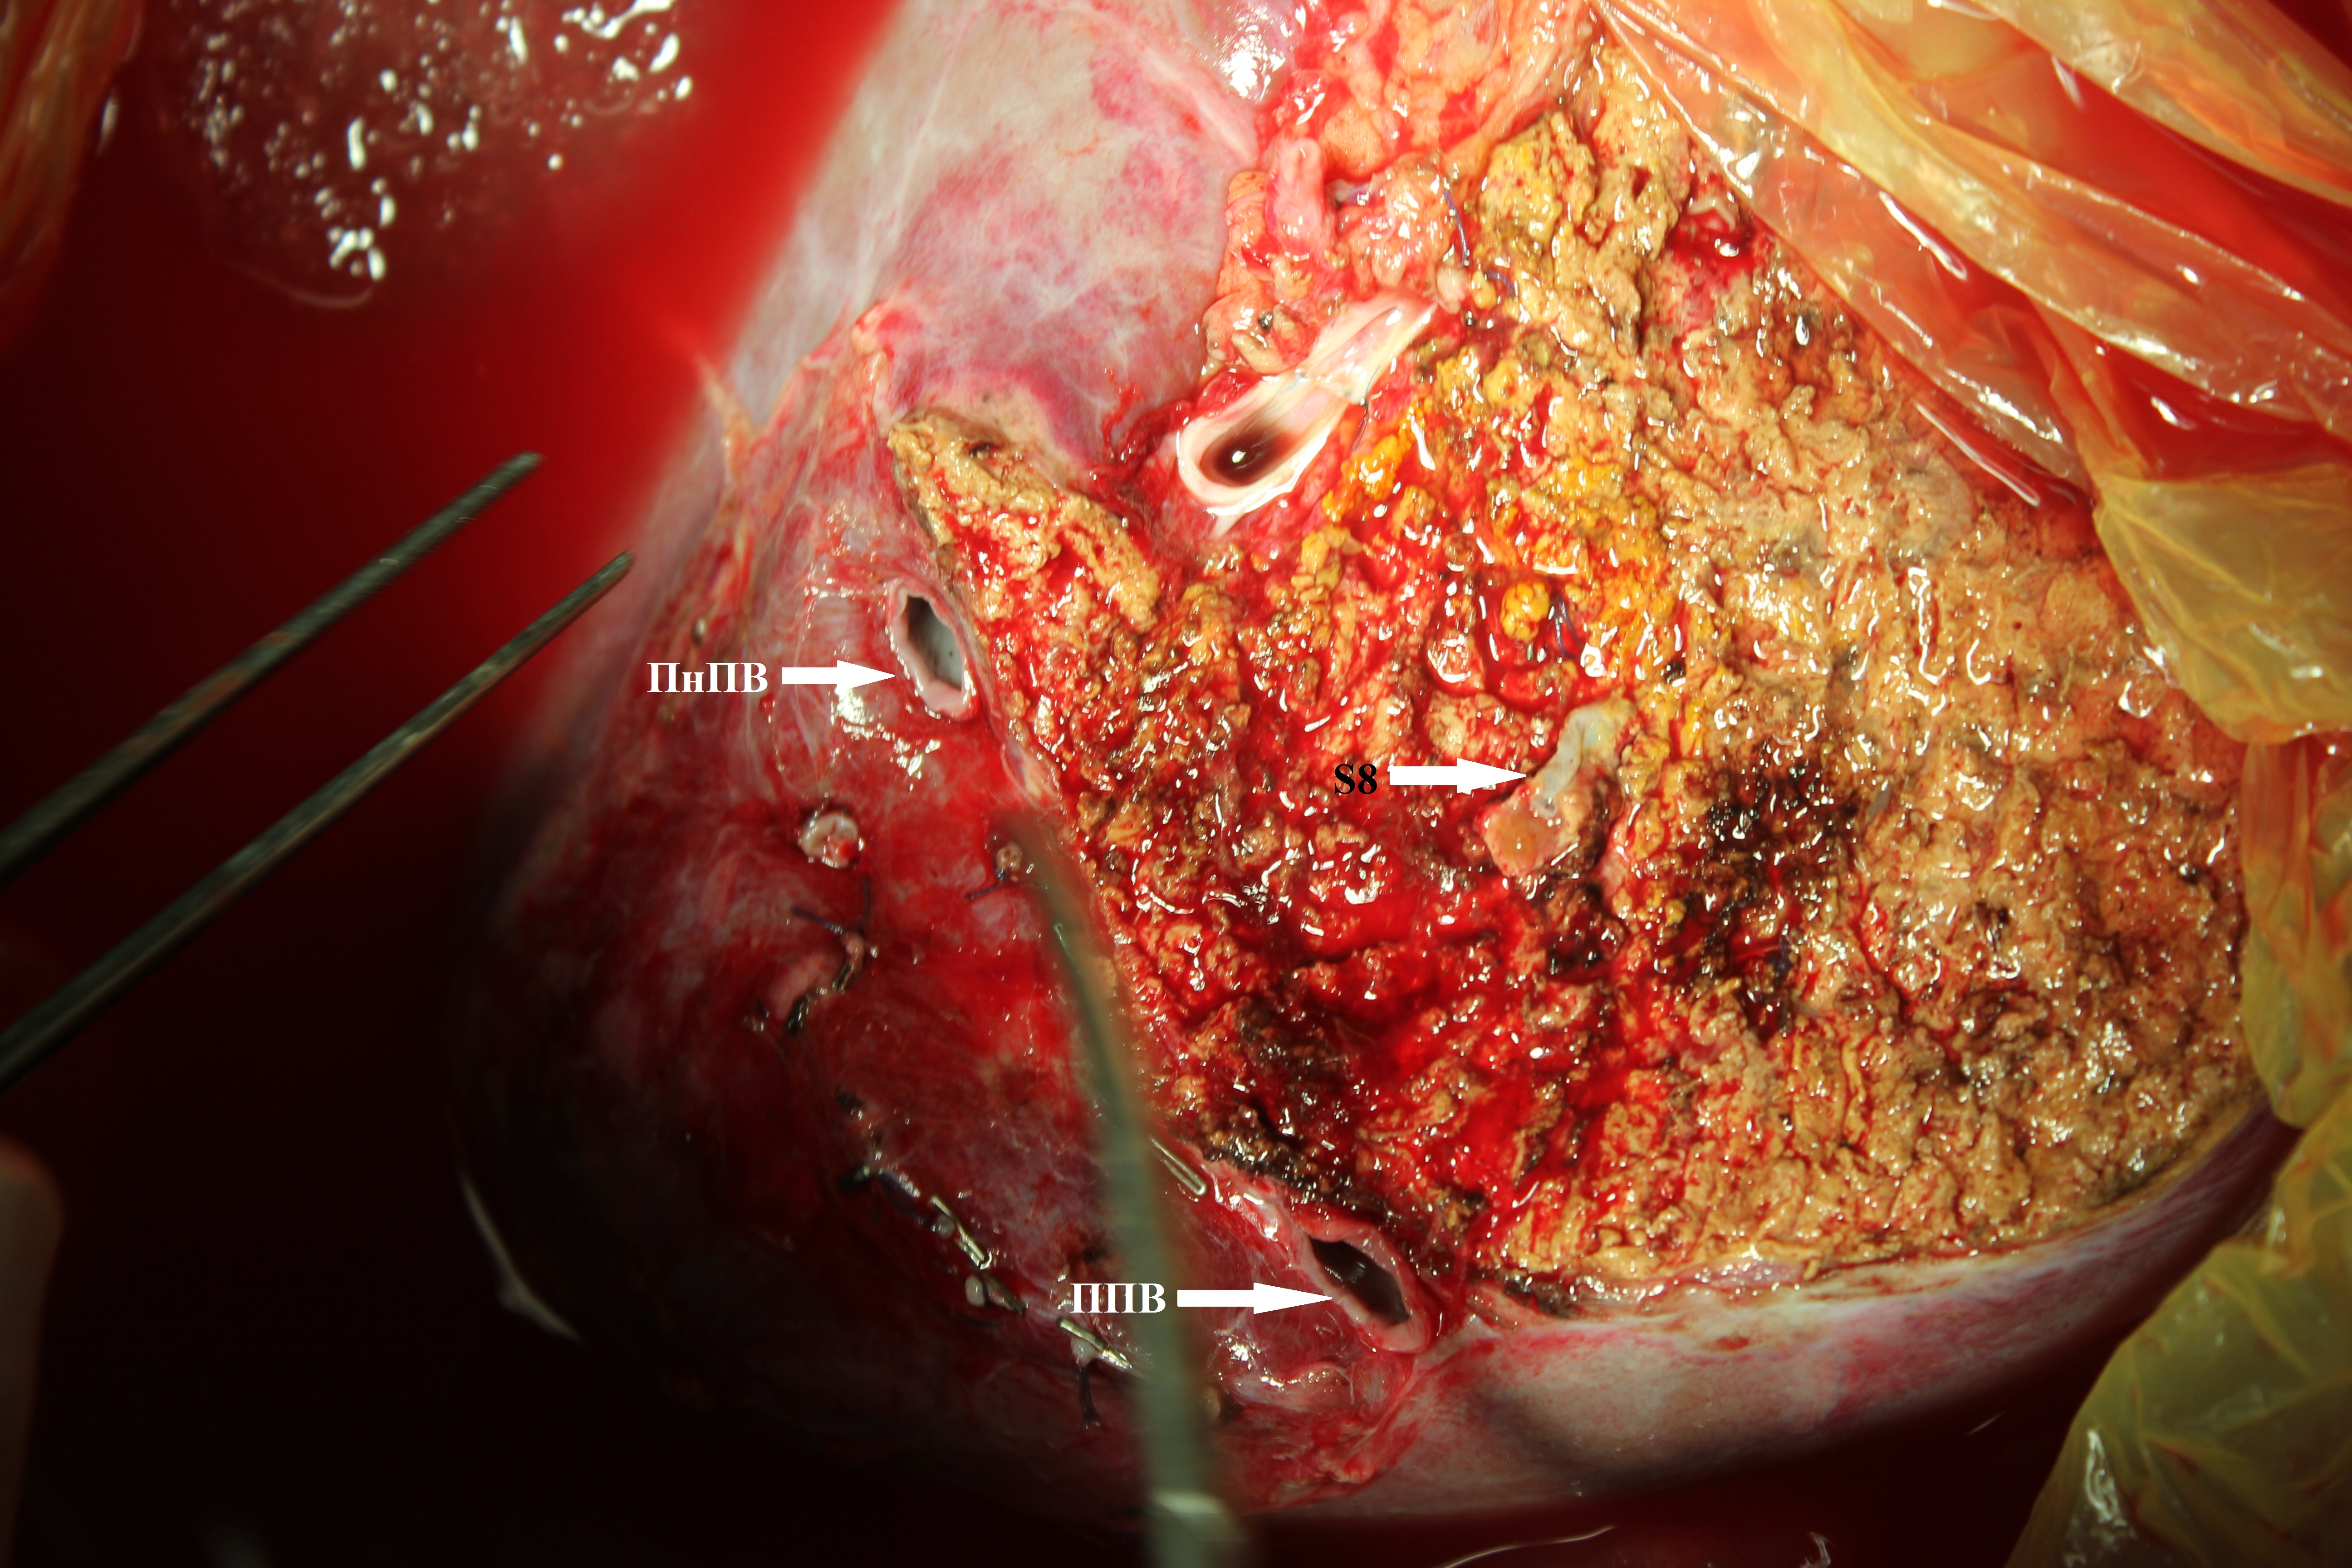

4. Тип А (фото). | |

| Тема | ||

| Тип | Исследовательские инструменты | |

Посмотреть

(2MB)

|

Метаданные ▾ | |